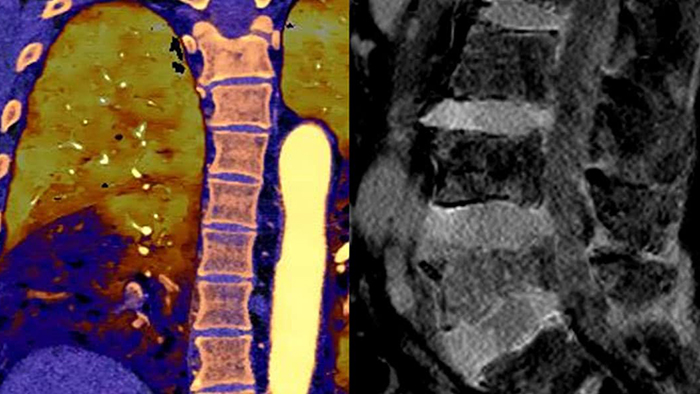

Spectral detector CT transformed conventional CT to a quantitative CT. The second-generation Philips Spectral CT 7500 receives an Aunt Minnie Award for Best New Radiology Device in 2021.

Unlike traditional CT images, spectral-detector CT images capture spectral information 100% of the time —without special planning or set-up. That means you can analyze the spectral data in any image retrospectively, using a variety of spectral viewing tools. You can, for example, adjust the monoenergetic level or get Zeffective maps.

Spectral CT helps me objectively differentiate contrast staining from hemorrhage, obviating the need for additional follow up scanning and prolonged patient observation, which can result in reduced costs and radiation exposure to patients.1,2